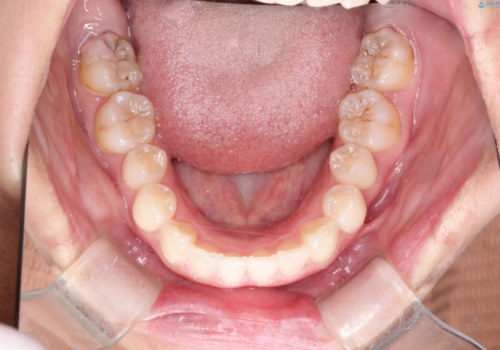

- 初診時には上顎前歯の突出、前歯部の深いかみ合わせ、叢生が見られる状態でした。

インビザラインにて不正咬合の原因除去を行うシミュレーションを念入りに制作の上、治療を行いました。

使用したインビザラインのマウスピース枚数:42枚+25枚+22枚(初回マウスピース+リファインメントが2回、1週間に1枚ペースでの交換)

このケースでは非抜歯にて奥歯を後方に移動させる事で前歯の突出を改善するスペースを作り出していますが、これはマウスピースと顎間ゴムの併用によるもので、患者様のご協力の賜物と言えます。

深い噛み合わせについてはシミュレーション上の結果と、予期される実際の歯の移動量とを考慮し、特殊なセットアップを行う事で望ましい結果を得ることができました。

治療途中でリファインメントという追加のマウスピースを製作する手順を行っていますが、その際に上下の正中を合わせたいとの要望があったため、追加シミュレーションの際に追加でセットアップを施しましたが、無事、上下の正中もご要望通りに改善しています。

使用した装置はマウスピースと顎間ゴムのみです。ワイヤーやマイクロインプラントなど補助装置の使用はありません。